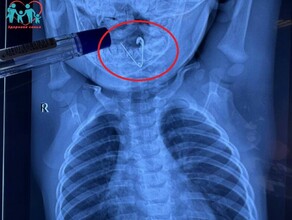

Фото: Telegram Амурские спасатели